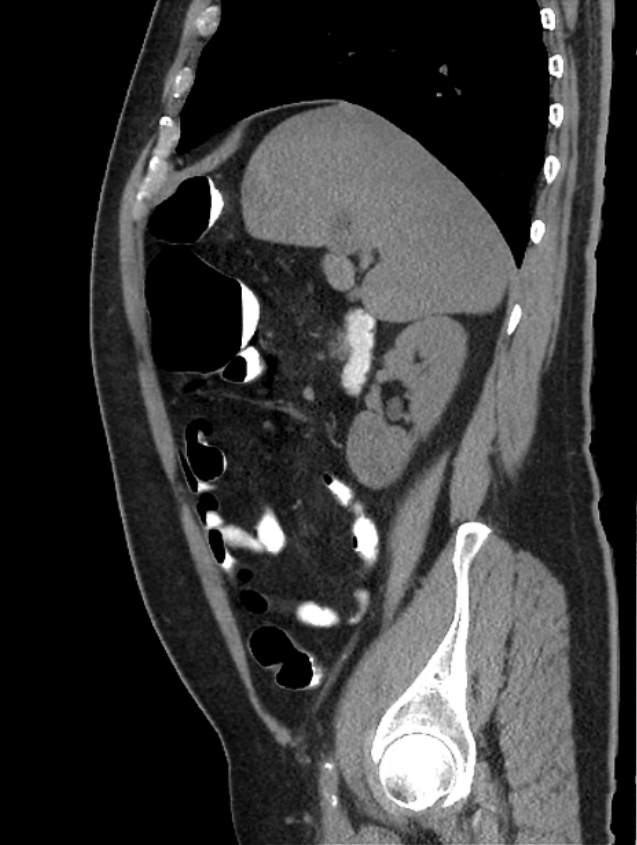

Chilaiditi

Chilaiditi - Ảnh 2

» Thông tin: Nam giới – 48 tuổi.

» Lâm sàng: Đau mạn sườn phải 1 tháng.